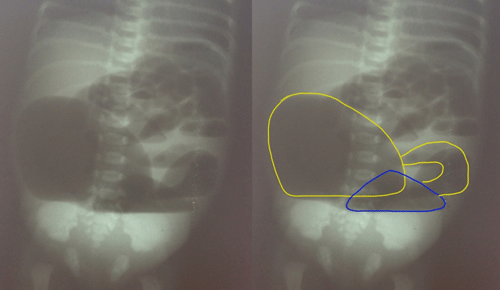

A 3-day-old term male child weighing 2.1 Kg, born by spontaneous vaginal delivery, was admitted with complaints of abdominal distention, meconuria and absent anal opening. This was the first child of the couple who had a non-consanguineous marriage. On examination, there was abdominal distention, poorly developed gluteal folds and an absent anal opening. Plain X-ray abdomen showed two large air fluid levels (Fig. 1). At exploratory laparotomy, Saxena-Mathur classification type 5 congenital pouch colon (CPC) was found. Ileum was opening directly into a hugely distended pouch; there was no appendix. The pouch was dumbbell shaped with normal looking intervening colon of about 5 centimeters. The dumbbell shaped pouch (proximal and distal components) was opening into the bladder through a wide fistula. The proximal part of intervening colon was not communicating with the proximal pouch but was intimately adherent to it. However, the distal part of the intervening colon was communicating with the distal pouch. Both the dumbbell shaped pouch and the terminal colon were receiving blood supply from a prominent marginal vascular pattern (Fig. 2). The distal pouch and intervening normal-looking colon appeared dusky with doubtful viability, so it was excised. Tubularized proximal pouch was brought out as end colostomy. The histopathological examination revealed the disorganized muscles in the muscularis layer of pouch colon; the intervening colon had normal colonic histology though there was evidence of congestion. The child is awaiting definitive repair.

Figure 1: Radiological film demonstrating type 5 CPC.(Left- unedited; right- markings showing double pouch colon with short normal inter-positioned colon segment). |